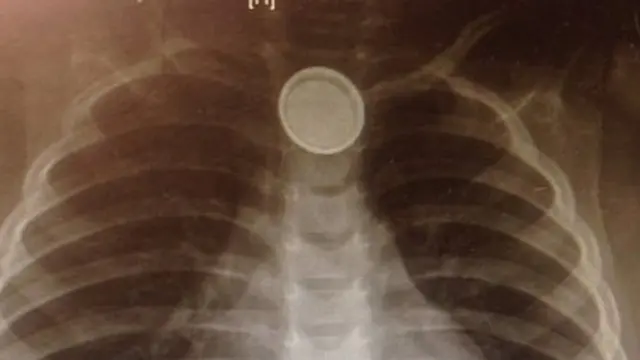

Lima hari kemudian diketahui melalui X-ray bahwa ia menelan baterai yang telah menyebabkan lubang saluran cerna dan saluran udaranya.

Bila tertelan secara tak sengaja, baterai kecil berbentuk seperti kancing ini dapat menyumbat saluran cerna dan menyebabkan lubang di kerongkongan karena lapisannya terbakar.

Kate Cross, dokter bedah anak mengatakan, "Bila baterai masuk kerongkongan, akan menciptakan sirkuit listrik dan baterai mulai berfungsi, dan mengeluarkan alkali yang mirip dengan soda dan merusak dinding saluran udara."